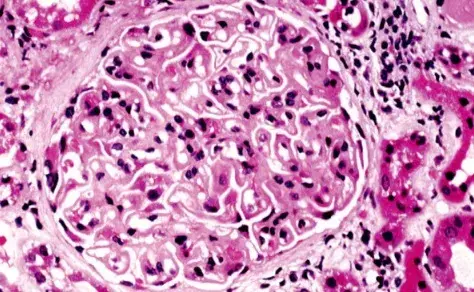

Nefropatía Membranosa: ¿Y si el paciente no responde al tratamiento inicial?

Nefropatía Membranosa: ¿Y si el paciente no responde al tratamiento inicial?

Cómo tratar la Nefropatía Membranosa de manera práctica

Cómo tratar la Nefropatía Membranosa de manera práctica